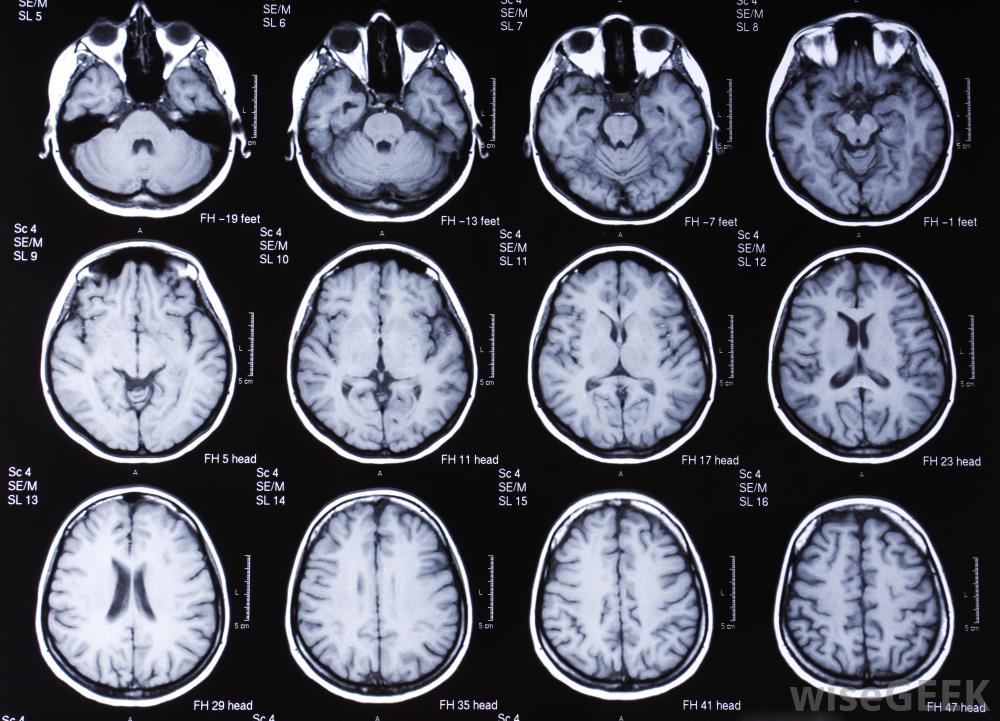

头部的MRI扫描通常用于帮助确定脑损伤的严重程度。大脑控制着人体的大部分功能。当个体遭受脑外伤时,他可能会丧失日常生活中所必需的基本功能。大多数脑损伤康复治疗的目的是教会个人如何变得自给自足。这包括进食、洗漱和,以及一般的卫生责任。